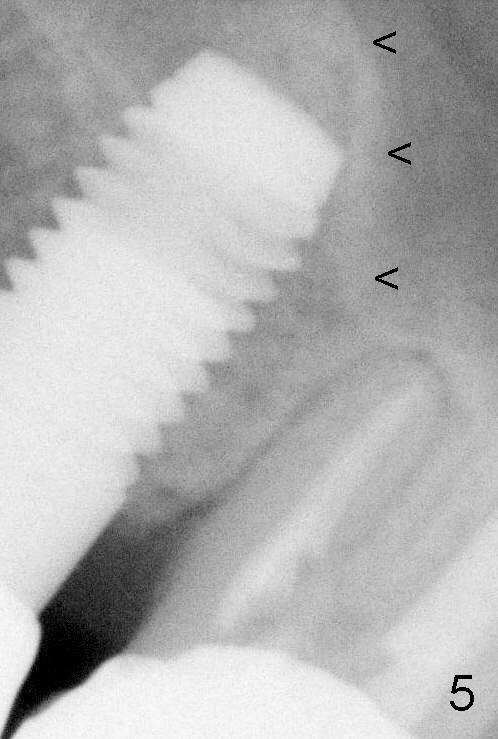

A 5x14 mm cylindrical implant (Fig.3 I) was inserted with elevation of the apparent sinus floor (>, no allograft used in case of sinus infection). Seven months postop, the density of sinus floor increases (Fig.4 <). The implant is stable and processed for crown (Fig.5 C, different view of the lifted sinus floor (<)). While sinus floor density is decreasing, the mesial and distal bone density is increasing 6 months (Fig.6), 1 year 6 months (Fig.7) and 3 year 6 months (Fig.8) post cementa-tion.